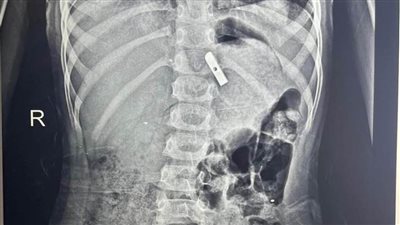

الأطفال التخصصي ينجح في استخراج "مسمار دباسة" اخترق جدار بطن طفل بالقليوبية

الخميس 02/أكتوبر/2025 - 12:53 م